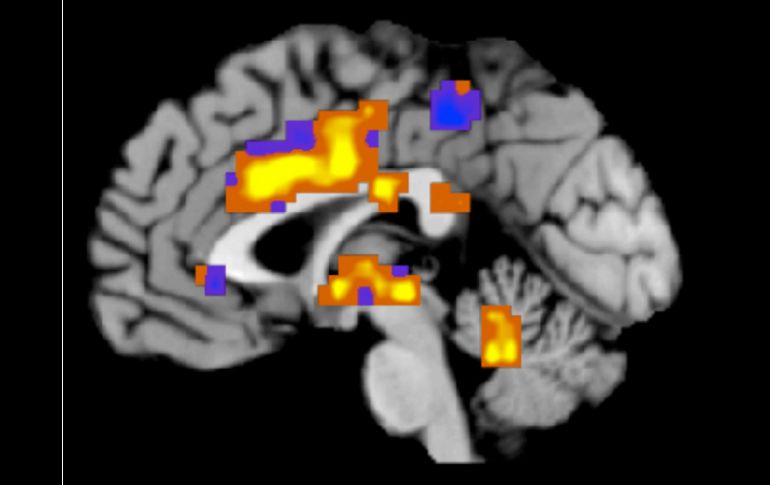

Tecnología | Aseguran que el efecto se presenta sin importar que se trate de una sinfonía o rock Escuchar música nueva gratifica al cerebro Aseguran que el efecto en la actividad cerebral se presenta sin importar que se trate de una sinfonía o rock pesado Por: EFE 11 de abril de 2013 - 19:54 hs Estudios demuestran que la dopamina interviene en esta respuesta en las áreas estriadas del cerebro. AFP / WASHINGTON, ESTADOS UNIDOS (11/ABR/2013).- Escuchar música nueva gratifica al cerebro y no importa si es un tango en la mañana, una sinfonía al atardecer o una noche de rock'n'roll estridente, según un artículo que publica hoy la revista Science. El estudio lo llevaron a cabo científicos del Instituto neurológico de Montreal (Canadá), y la Universitad de Utrecht (Holanda), entre otros, empleando la imagen funcional por resonancia magnética que capta figuras del cerebro durante la actividad. La música, explicaron los investigadores, ha sido un fenómeno muy poderoso que existe en todas las culturas desde la prehistoria pero en gran medida sigue sin saberse cómo los sonidos pueden convertirse en algo tan placentero. Otros estudios ya han demostrado que el escuchar música afecta e involucra no sólo la corteza auditoria del cerebro sino también las regiones de las emociones y los circuitos mesolímbicos vinculados con la gratificación. Hay estudios que han demostrado que la dopamina interviene en esta respuesta en las áreas estriadas del cerebro. "Estos circuitos de gratificación refuerzan comportamientos biológicamente adaptativos que incluyen el comer y el sexo y los comparte la mayoría de los vertebrados", explicó el estudio. Pero la apreciación de la música es compleja y, aparentemente, una característica distintiva de los humanos, y depende de factores socioculturales, las experiencias y las memorias. Temas Ciencia Música Cerebro Lee También ¿Bad Bunny fuera del Super Bowl? Este sería el show alternativo Fallece John Lodge, bajista de The Moody Blues Los mejores eventos de entretenimiento del 10 al 16 de octubre de 2025 Fiestas de Octubre 2025: cartelera por fecha en el Auditorio Benito Juárez Recibe las últimas noticias en tu e-mail Todo lo que necesitas saber para comenzar tu día Registrarse implica aceptar los Términos y Condiciones